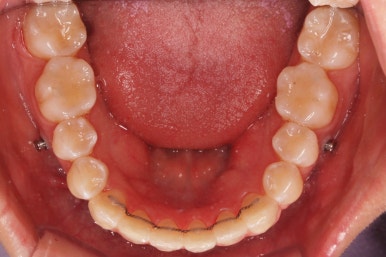

틈은 다 다물어졌고, 부가적인 정교한 마무리 과정을 더 거치게 됩니다.

중앙선도 잘 맞고 교합도 잘 마무리되었습니다.

이 뽑은 자리가 다시 벌어지지 않게 앞니가 다시 틀어지지 않게 유지철사를 부착하고 마무리를 하였습니다.

전후 비교해 보겠습니다.

중앙선, 교합, 뻐드러짐 모두 좋아졌고 이를 뽑고 교정했지만 발치 공간이 남지 않고 잘 마무리 되었습니다.